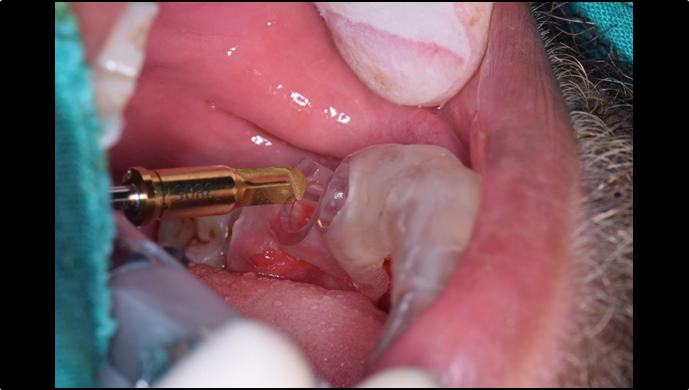

Clinical case: : Immediate loading of lower molars using R2Gate prefabricated 3D-printed provisional restoration

- Courtesy of Dr. Sam Omar, Egypt -